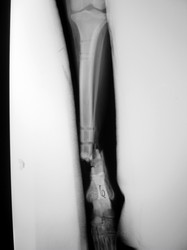

Fijación Externa

PRÁCTICAS CURSO DE FIJACIÓN EXTERNA PERFECCIONAMIENTO.

Híbrido.